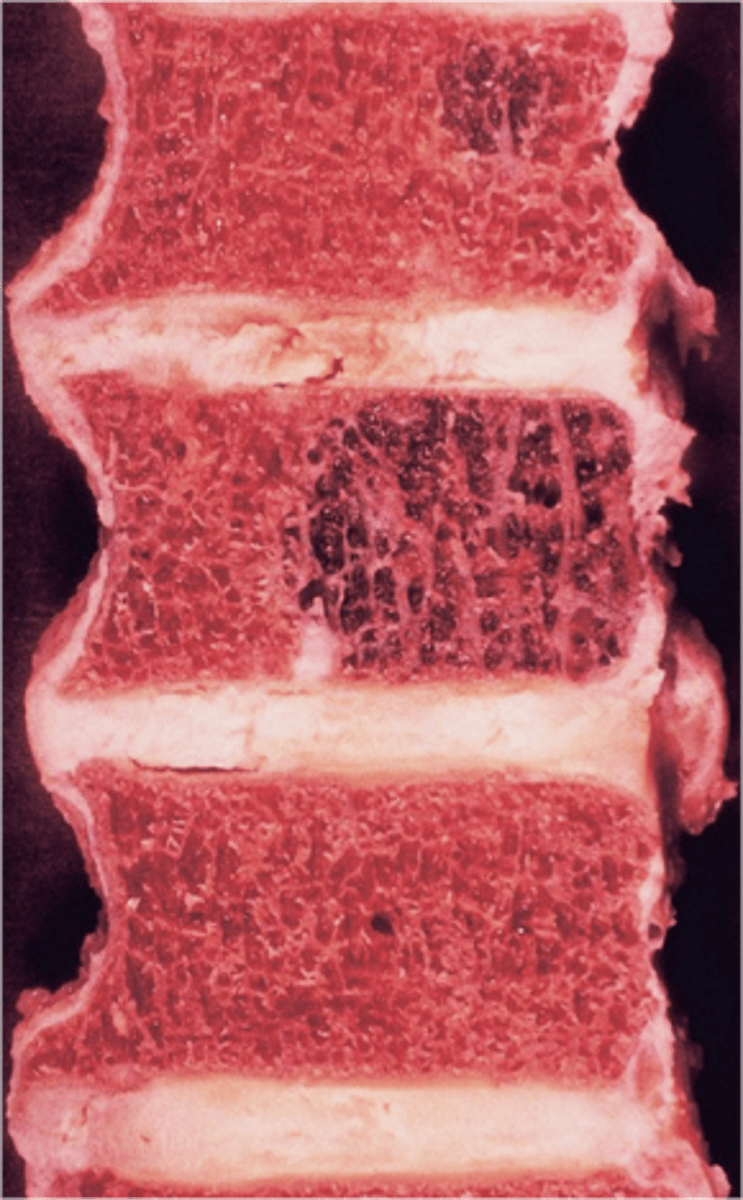

Vertebral hemangioma

- Solitary vascular neoplasm

- Slow growing

- 2-3% of all spine tumors (radiographs)

- 11% of all spines (autopsy)

- Most common benign tumor of the spine

State the incidence of vertebral hemangioma

- First seen over 40 y.o.

- F>M

- Most asymptomatic

- 75% in spine and skull

- Lower thoracic and upper lumbar

- Vertebral body

• Extension into vertebral arch (10-15%)

State the clinical features of vertebral hemangioma

- Vertical striations (corduroy cloth)

- Expansion (rare) may result in neurologic findings

- Skull ("sand dollar")

- Paravertebral swelling

State the radiographic features of vertebral hemangioma

Expansile

_____ vertebral hemangioma

- Left: Paget Disease

- Middle: Vertebral hemangioma

- Right: Osteoporosis

Complete the DDx for vertebral hemangioma